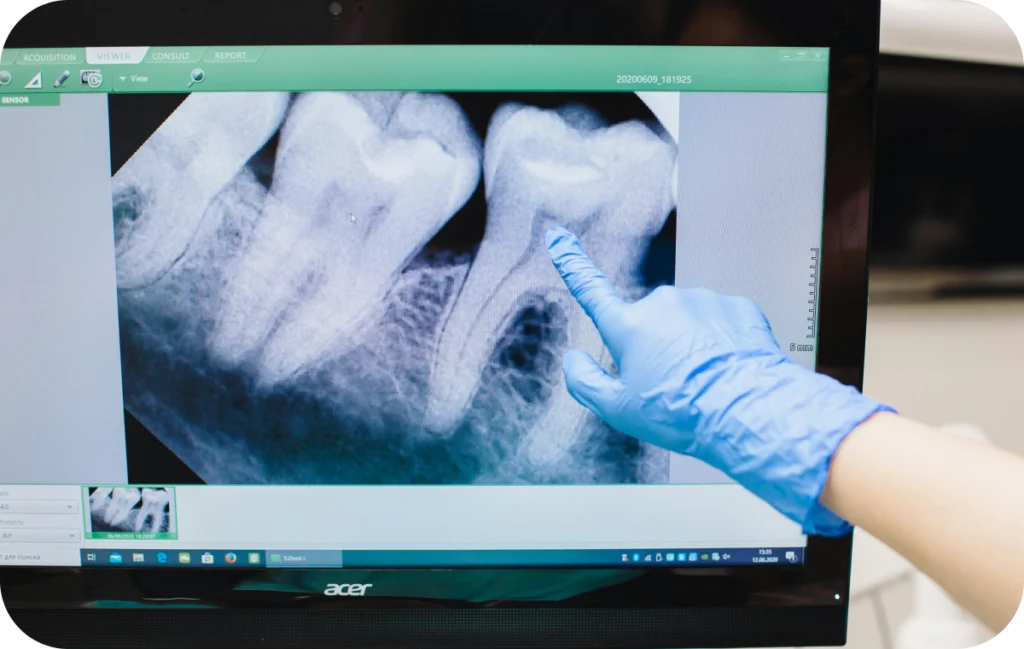

Le recours à l’endodontie est souvent motivé par des symptômes précis. Une douleur persistante, une sensibilité marquée à la chaleur ou au froid, ou encore une douleur à la mastication sont des signaux qui peuvent indiquer une atteinte de la pulpe. Parfois, l’infection peut évoluer de façon silencieuse et être découverte lors d’un examen radiographique de contrôle.

L’endodontie est une discipline de la dentisterie qui s’intéresse à la partie interne de la dent, appelée pulpe dentaire. Cette zone, protégée par l’émail et la dentine, contient les nerfs et les vaisseaux sanguins qui assurent la vitalité de la dent. Lorsqu’elle est infectée ou gravement atteinte par une carie ou un traumatisme, il est nécessaire d’intervenir pour soulager la douleur et préserver la dent.

Un traitement endodontique, souvent appelé traitement de racine, consiste à retirer les tissus infectés, à désinfecter les canaux internes puis à les obturer de manière hermétique. L’objectif est de conserver la dent dans la bouche du patient, en évitant une extraction.